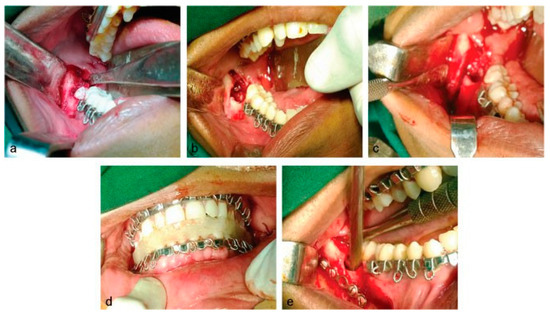

Isolated Bilateral Mandibular Angle Fractures: An Extensive Literature Review of the Rare Clinical Phenomenon with Presentation of a Classical Clinical Model

Case Report